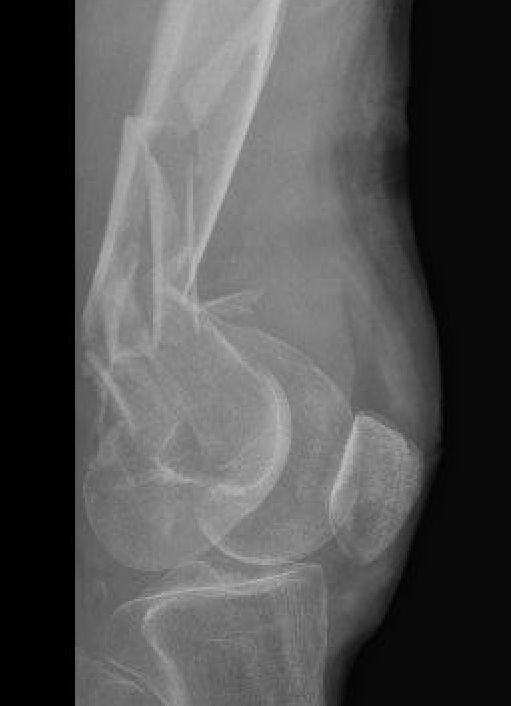

Xray

Options

Lateral plate

Retrograde IM nail